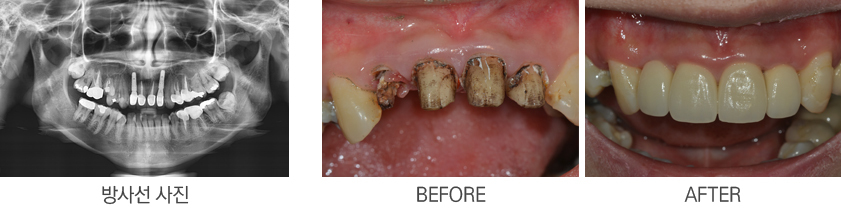

¾Õ´Ï ÀÓÇöõÆ®

: ¾Õ´Ï ÀÓÇöõÆ®